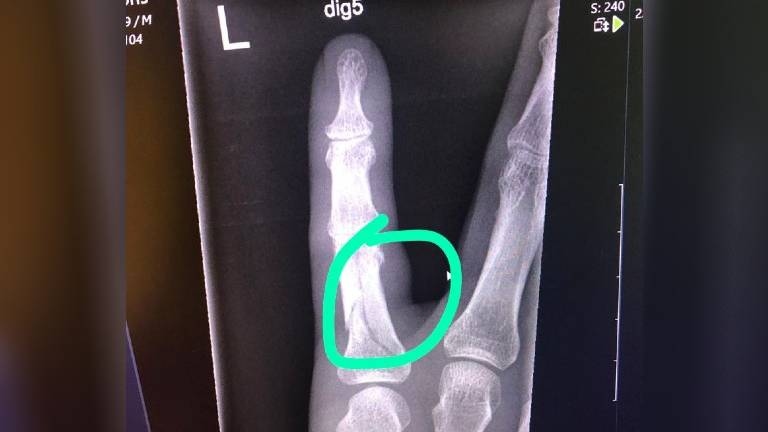

Het algoritme ontdekte tijdens de testfase, waarin het zeshonderd recente foto's analyseerde, zelfs zeven breuken die door professionals niet waren opgemerkt.

"Uit onze test bleek dat BoneView in staat is om fracturen te vinden die de specialisten met het blote oog niet zagen", zegt radioloog Erik Ranschaert. Als de onderzoeksresultaten worden doorgetrokken naar een heel jaar, zouden in het ziekenhuis per jaar 360 tot 370 gemiste breuken opgespoord kunnen worden, voegt hij eraan toe. "Dat is toch een aanzienlijk aantal."

De software beoordeelt in 3 minuten een röntgenfoto en kan in de meeste gevallen met zekerheid zeggen of iemand een fractuur heeft. De uitkomst kan ook 'twijfel' zijn. Dan staat er een stippellijn op de plek waar de mogelijke breuk zit en moet de radioloog alle foto's goed bekijken en zelf de knoop doorhakken.